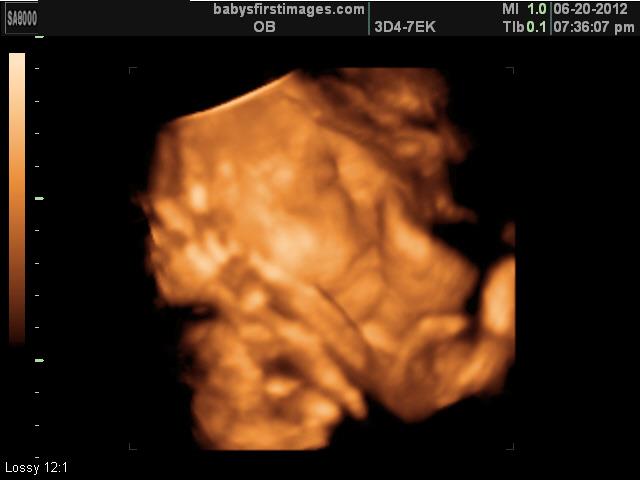

Second 3d/4d Ultrasound

We didn't get the best photos ever, but its our precious baby boy & we feel blessed either way that we got the chance to experience seeing him again before he arrives in 3d/4d. We also got a video, LOVE it. All of the pictures he has his hands up & thumb in his eye, he didn't want to change out of that position!! The second picture is the BEST one we got & it just happens to be of his privates lol!! This ultrasound was done at 31 weeks :)